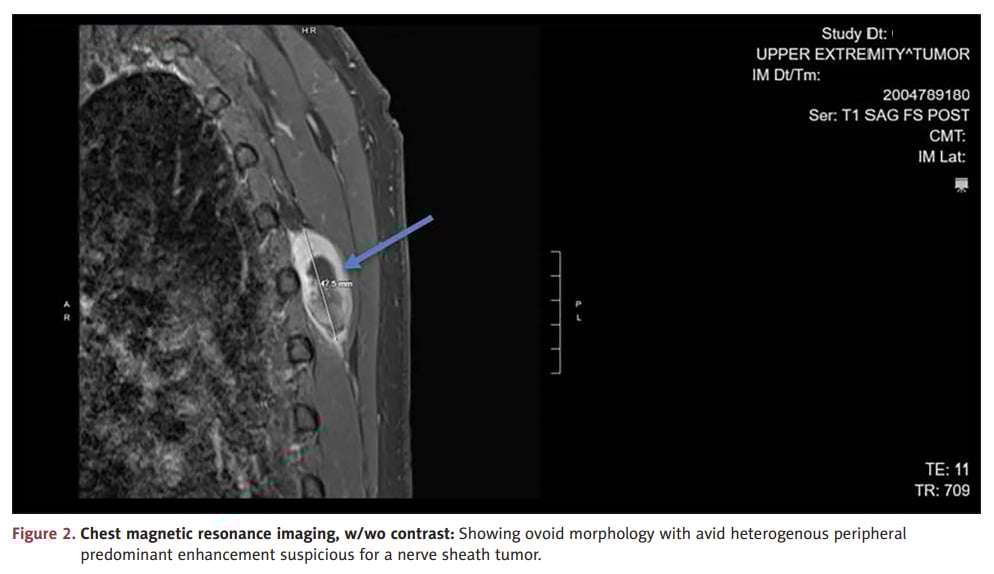

MRI有助于评估肿瘤范围、强化特征及邻近组织受累情况。

- 影像提示肿块强化不均、中央坏死、邻近组织浸润